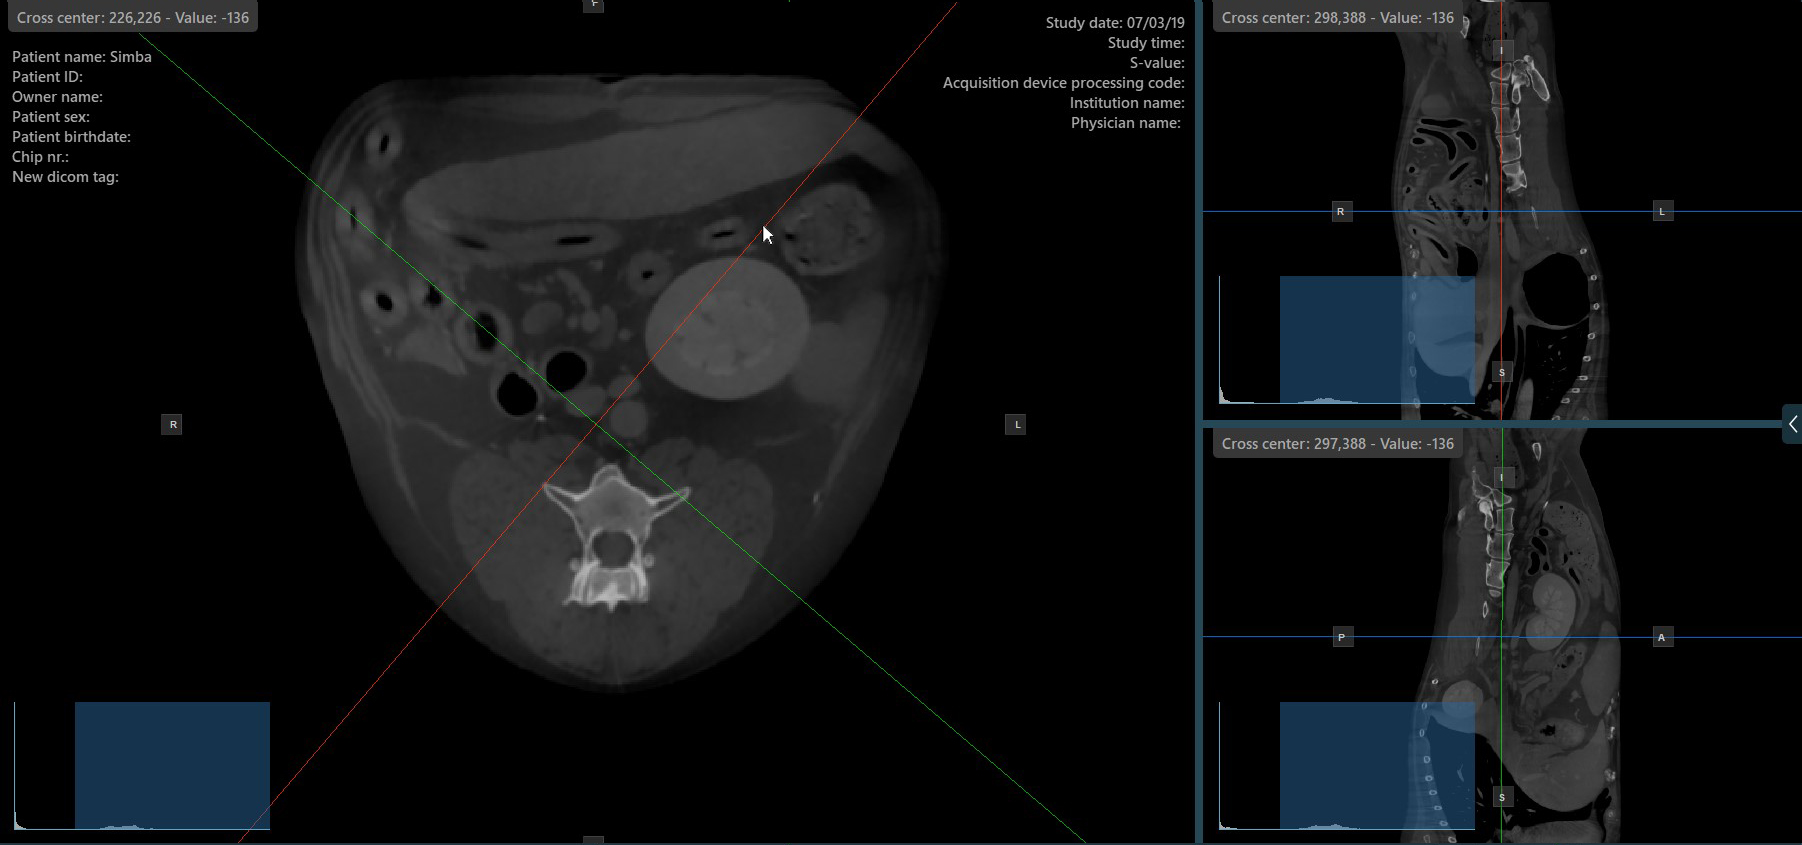

Press the Perpendicular Slicers icon in the left toolbar to activate simultaneous rotation of the slicers. Regardless of their previous orientation, the slicers are repositioned to be perpendicular to each other.

Toggle the Perpendicular Slicers option to switch the active mode of the slicers at any time, or choose one of the Tools -> Perpendicular Slicers or Tools -> Separate Slicers options from the CT Viewer menu.